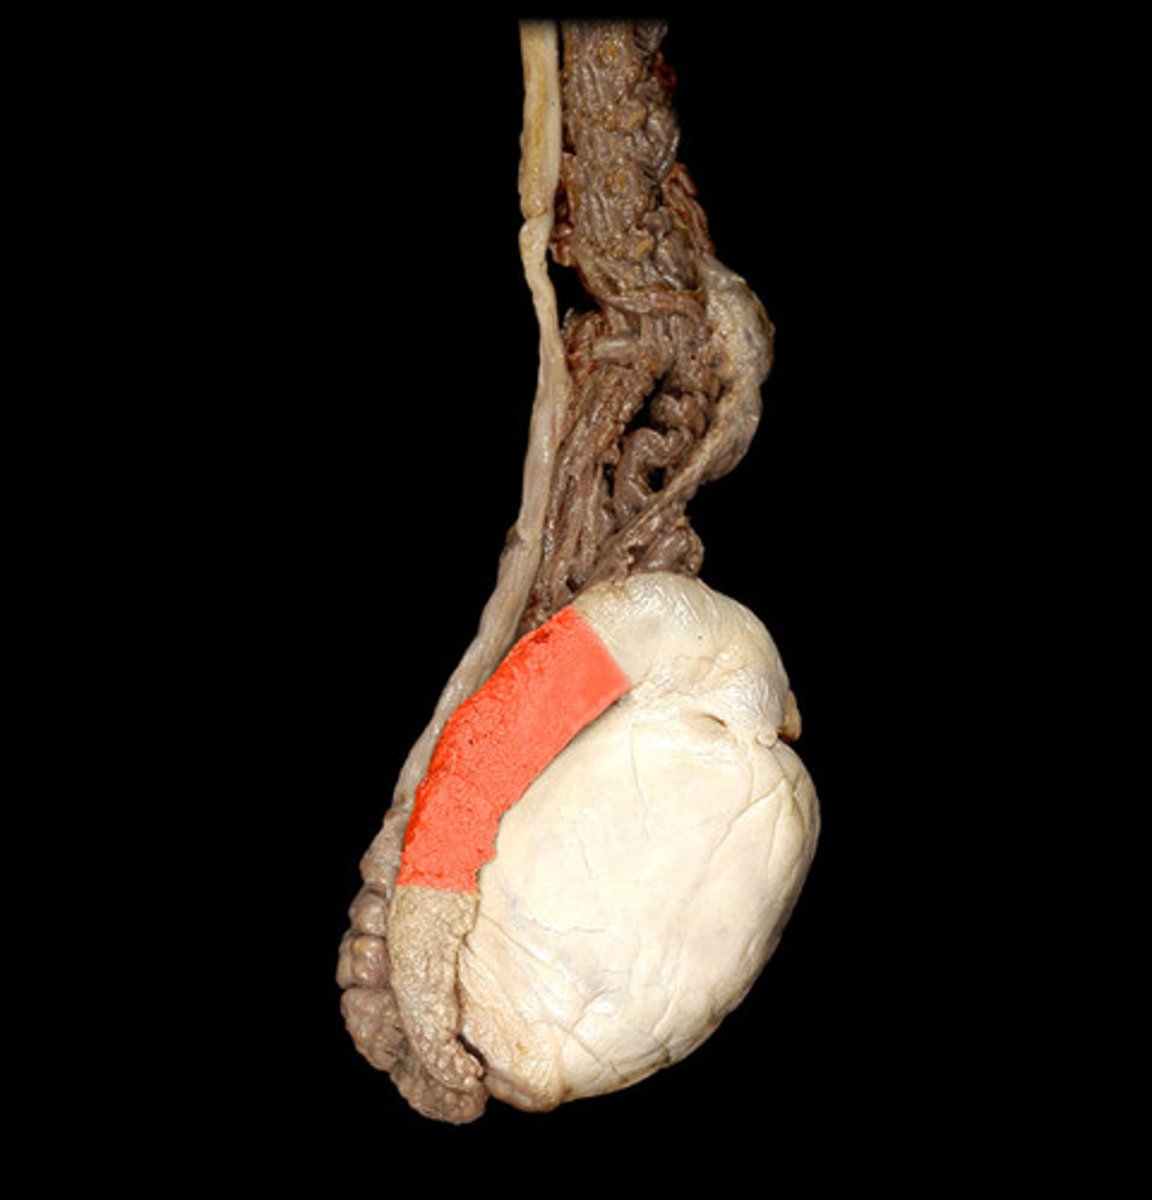

testis

tunica albuginea

epididymis head

epididymis body

epididymis tail

spermatic cord

vas deferens